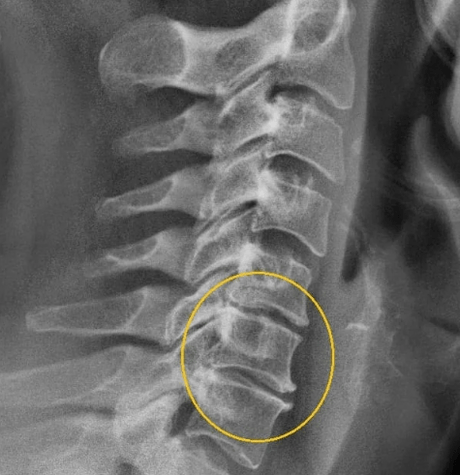

Stage III

The fibrous rings on the disk are destroyed, hernia is formed. In the third stage, there is a deformity of the spine, displacement and vertebrae displacements due to their weak fixation. Symptoms are as follows:

This is a severe stage of the disease in which the patient is no longer able to support his head himself. Spinal cord ischemia and compression of the spine arteries lead to a complete inability to move and reduce forces in the muscles in other parts of the body, as well as to damage the spinal cord.